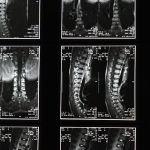

La décompression vertébrale est une technique thérapeutique qui consiste à appliquer une force contrôlée sur la colonne vertébrale pour réduire la pression sur les disques intervertébraux. Cette méthode permet de mieux gérer les douleurs dorsales en favorisant la circulation sanguine et en diminuant la tension sur les nerfs. Elle est particulièrement bénéfique pour les personnes souffrant de hernies discales ou de lombalgies.

La décompression vertébrale travaille en appliquant des tractions spécifiques sur la colonne vertébrale. Cela permet de créer un espace entre les vertèbres, réduisant ainsi la pression exercée sur les disques intervertébraux. Ce processus contribue à améliorer la circulation sanguine et à faciliter la récupération des zones endommagées. Les patients présentant des douleurs chroniques, souvent causées par des hernies discales ou des compressions nerveuses, trouvent dans cette méthode un véritable soulagement.

La décompression neurovertébrale est une méthode thérapeutique non invasive qui pourrait être la solution que vous recherchez. Elle est spécialement conçue pour soulager les douleurs associées à des pathologies discales sévères, notamment les hernies discales et les sténoses spinales. En utilisant une traction douce et contrôlée, cette technique réduit la pression sur les disques intervertébraux et les nerfs, favorisant ainsi la rétraction du matériel discal hernié. Imaginez pouvoir retrouver une meilleure qualité de vie et enfin dire adieu à des douleurs persistantes qui ont entravé votre quotidien.